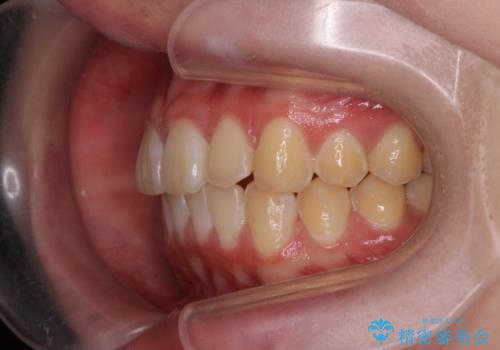

前歯のがたつき気になる。インビザラインモデレート

- 前歯のがたつきが気になるとの事で来院。

マウスピース矯正希望でしたのでインビザラインモデレートで治療を行いました。

がたつきが無くなり満足して頂けました。

矯正が終わった後は保定装置を使用しないと後戻りしてしまうのでしっかりと保定装置を使用する必要があります。